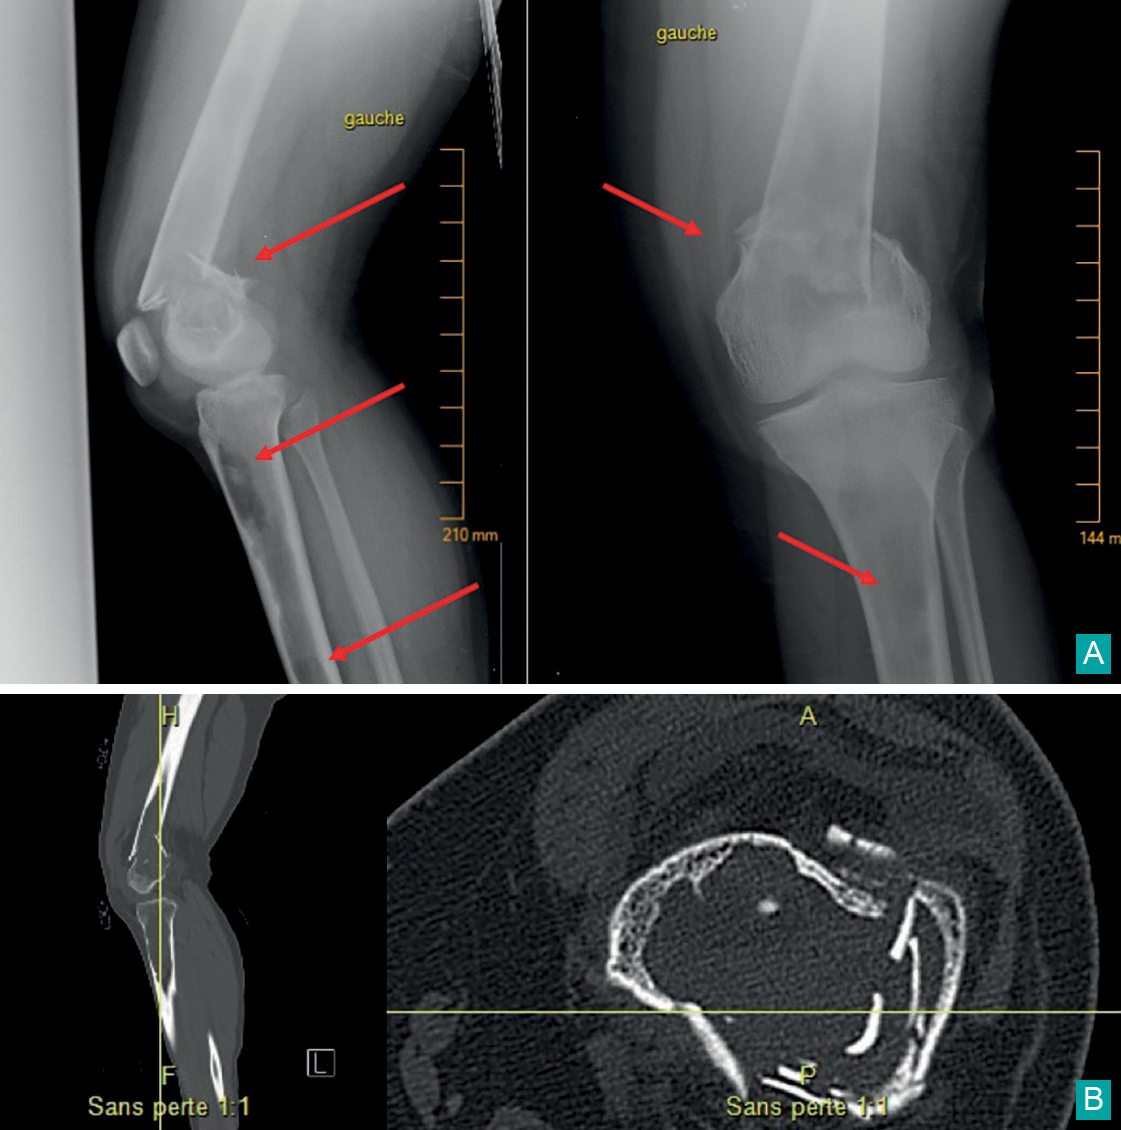

Marin Tardy, La Revue du Praticien A. Fracture fermée comminutive déplacée, supracondylienne, du fémur à la radio. B. Kystes lacunaires au scanner.